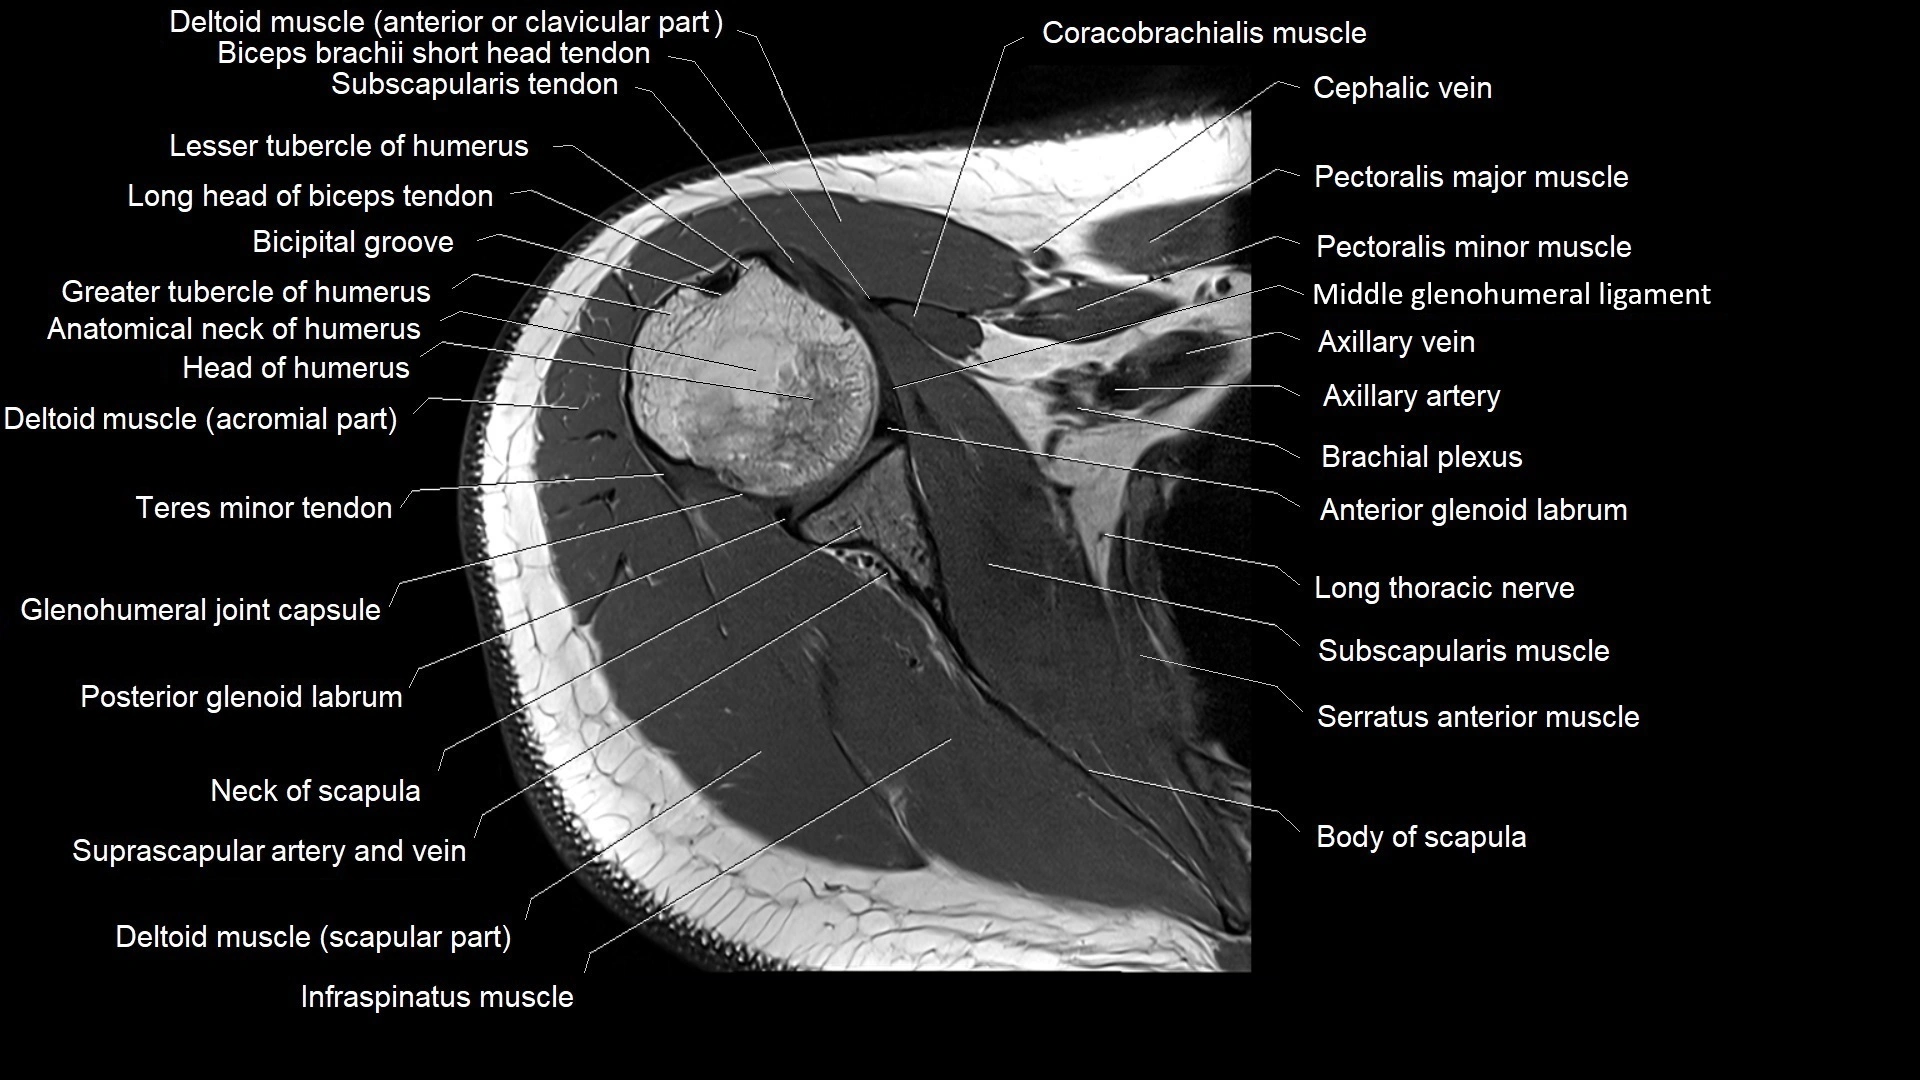

MRI images

image